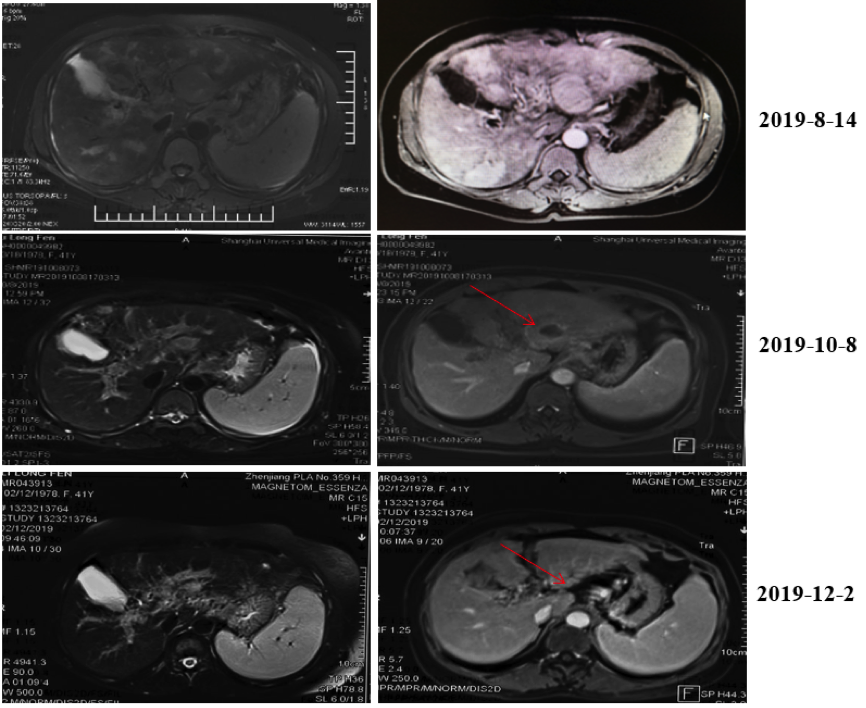

2019年8月14日基线检查上腹部增强MRI提示:肝左外叶肝细胞肝癌(3.6cm×3.6cm),肝内子灶形成可能,门静脉主干及分支癌栓形成,肝硬化,脾大,腹腔积液,食管下段胃底静脉曲张(图1)。1.png

图1. 2019年8月14日腹部MRI肝内可见肝内多发占位伴门脉癌栓